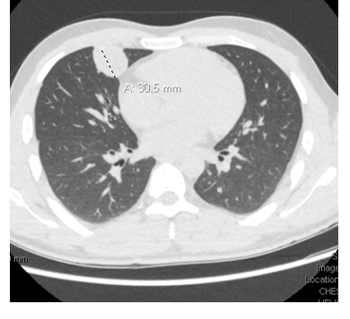

This unusual Case Study describes a young woman who presented with an acute onset of headaches and dizziness and was found to have aseptic meningitis.